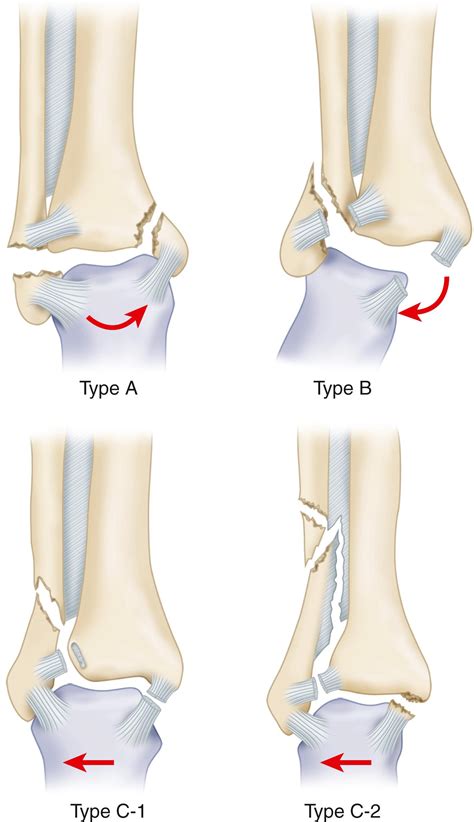

The Weber classification system is widely used to categorize ankle fractures based on the level of the fibular fracture in relation to the syndesmosis, which is the ligamentous connection between the tibia and fibula. The system is divided into three main types: Weber A, Weber B, and Fracture Weber C.

Weber A Fractures

Weber A fractures occur below the level of the syndesmosis. These fractures are typically stable and involve the lateral malleolus. Treatment often includes immobilization and non-weight-bearing for a period, followed by physical therapy to regain strength and mobility.

Weber B Fractures

Weber B fractures occur at the level of the syndesmosis. These fractures are more complex and can involve instability of the ankle joint. Treatment may require surgical intervention, such as open reduction and internal fixation (ORIF), to realign the bones and stabilize the joint.

Fracture Weber C

Fracture Weber C injuries are the most severe and occur above the level of the syndesmosis. These fractures are often associated with significant instability of the ankle joint and may involve damage to the syndesmotic ligaments. Fracture Weber C injuries typically require surgical intervention to restore stability and alignment.